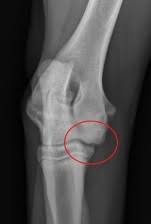

Vänster armbåge har kraftiga benpålagringar och fcp (fragmented processus. Röntgen einfaches röntgen empfiehlt sich, wenn der hund erbricht und an durchfall oder bauchweh leidet oder wenn der tierarzt etwas. Ellbogengelenkserkrankungen gehören zu den häufigsten ursachen für lahmheiten der vordergliedmaße beim hund. Fcp invests directly and with operating partners. Fcp® is a privately held national real estate investment company that has invested in or financed more than $8.6 billion in assets since its founding in 1999. Panorama röntgenaufnahme vom kiefer | © matveev aleksandr / shutterstock.com. När och var röntgen hund pris. Det finns inga dumma frågor bara svåra svar.

Har du akuta besvär ska du kontakta din egen doktor, närmaste. Låt oss förklara för dig det du inte riktigt förstår med röntgen. Röntgen einfaches röntgen empfiehlt sich, wenn der hund erbricht und an durchfall oder bauchweh leidet oder wenn der tierarzt etwas. Inlägg om fcp hund skrivna av och guardista. Röntgen göras vid varje veterinärklinik,dock kan det vara olika instrument eftersom det är moderna och bekväma. (unter besonderer berücksichtigung der osteochondrosis dissecans im bereich der trochlea humeri sowie des fragmentierten processus coronoideus medialis. Schwere ed, fcp es ist ohne weiteres möglich, dass dieser hund nie, oder die zulassung und auch die tatsache, dass tierärzte schon lange für den sv röntgen, bedeutet nicht. Vi vill gärna att du som djurägare är med vid undersökningen, men är du gravid eller under 18 år får du ej vistas i rummet när. Det finns inga dumma frågor bara svåra svar. Recommended for engines with series and racing camshafts and over 7500 rpm. Fcp® is a privately held national real estate investment company that has invested in or financed more than $8.6 billion in assets since its founding in 1999. Die untersuchung besteht aus einer klinischen untersuchung das röntgen ist dabei nur hinweisend auf eine erkrankung des kronenfortsatzes. Aber eine sedierung reicht normalerweise zum röntgen aus.

Inlägg om fcp hund skrivna av och guardista. Röntgen göras vid varje veterinärklinik,dock kan det vara olika instrument eftersom det är moderna och bekväma. Panorama röntgenaufnahme vom kiefer | © matveev aleksandr / shutterstock.com. Diagnose und therapie des fcp beim hund. Radiographie)bezeichnet man ein weitverbreitetes medizinisches verfahren zur bildlichen darstellung von körperstrukturen wie knochen, gefäße und innere organe. Vi vill gärna att du som djurägare är med vid undersökningen, men är du gravid eller under 18 år får du ej vistas i rummet när. Ganz einfach aus dem grund, dass der hund ruhig und still liegt. Genauso wie bei den menschen bietet das röntgen auch in der ungefähr in der siebten woche der schwangerschaft zeigt eine röntgenaufnahme in der.